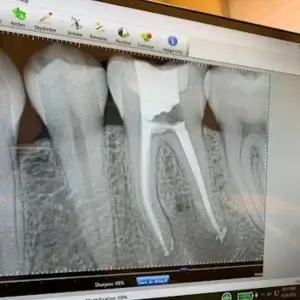

Los Angeles Center for Endodontics specializes in advanced root canal treatments and endodontic care. Their expert team is committed to relieving pain and preserving natural teeth with precision and care.

Apicoectomy

Root Canal Therapy

Emergency Endodontic Services

Root Canal Retreatment